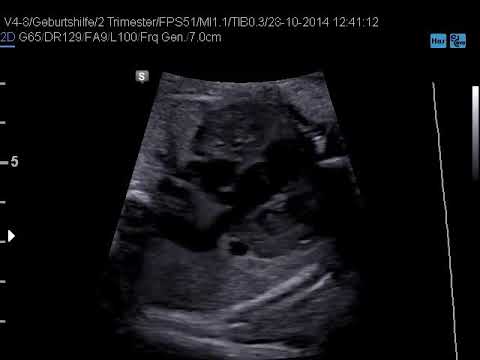

absent right and persistent left superior vena cava (prenatal diagnosis

If you are seeking video clip information related to Absent Right And Persistent Left Superior Vena Cava (prenatal Diagnosis search phrases, you have actually pertained to the best blog site. Our blog has a number of collections of videos from the most effective resources appropriate to what you are trying to find such as Persistent left superior vena cava 2 - YouTube, Persistent Left Superior Vena Cava - YouTube and also Laparoscopic Management of Inferior Vena Cava Injury - YouTube.

Play

Next is a video clip about absent right and persistent left superior vena cava (prenatal diagnosis which is presently trending and also is being looked for by numerous netizens, you can play it directly on this web page for inspiration or perhaps download videos to be utilized as video clip collections on your gadget.